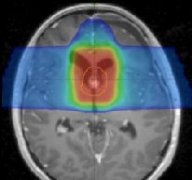

1放射治疗 新发H3 K27M突变型弥漫性中线胶质瘤患儿的治疗主要是病灶局部放射治疗,常规方法为三维适形放射治疗(3D-CRT),即6周内完成54~60Gy(1.80~2.00G...